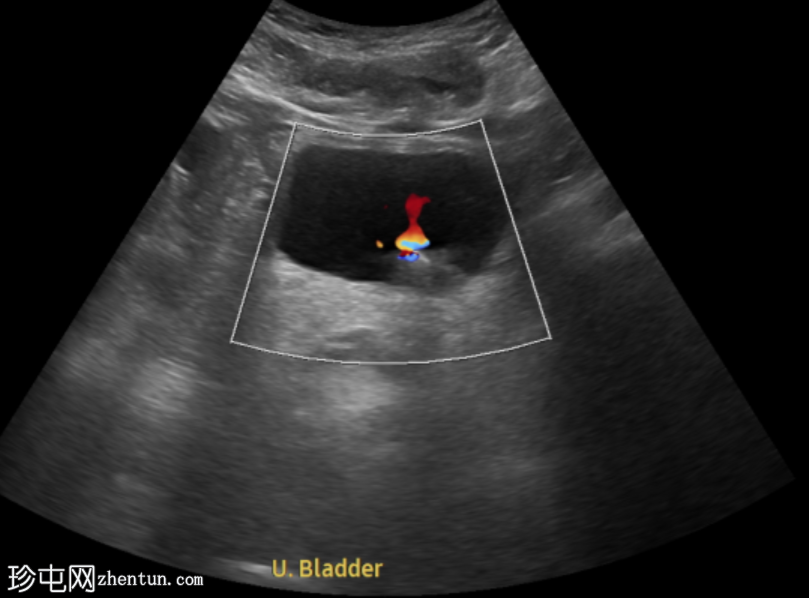

左侧腰痛伴血尿。

年龄:45岁

性别:男

超声

检查

超声显示左侧轻度肾积水,由膀胱输尿管连接处一枚7毫米的远端输尿管结石阻塞所致,输尿管射流正常。

肾积水并非总是由输尿管结石引起。肾盂和肾盏扩张的程度与结石大小并不一定相关。

较小的结石有时可导致中度上游扩张,而较大的结石可能仅引起轻微的充盈感,这取决于患者的引流和水合状态。